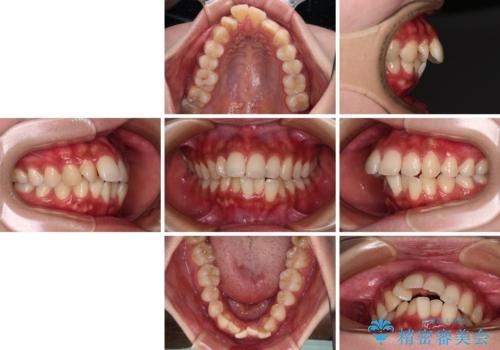

- 前歯の突出感とデコボコを気にして来院された患者様です。

奥歯の噛み合わせをみると、上顎歯列が全体的に前突している状態であり、この咬み合わせのまま歯列を整えると出っ歯になってしまう可能性がありました。

アンカースクリューと補助装置を使用して上顎大臼歯を遠心移動させることで咬み合わせを改善し、更には口元の突出感を改善するために上下左右の小臼歯4本を抜歯し、ワイヤー装置によりデコボコを解消しながら口元の突出感も改善していくこととしました。

上下の前歯が接触する仕上がりとなったので、横顔の印象が大幅に改善されました。